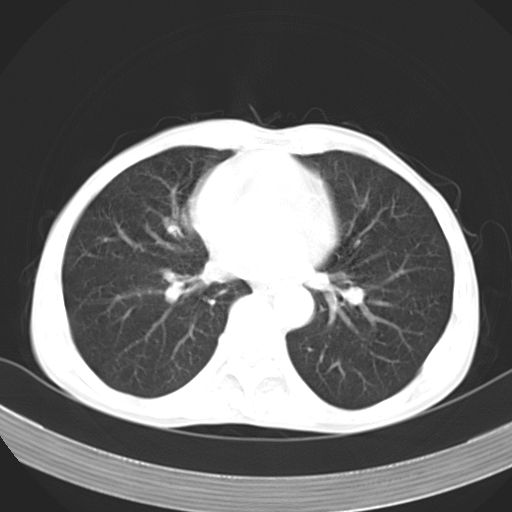

以下是引用苯小孩在2007-5-24 12:47:00的发言:[br]右侧肺门处不均匀密度软组织块影,远端肺组织见斑片模糊影,纵隔内淋巴结明显肿大,边界不清.<纵隔窗第12层面支气管内似见软组织结节>[br]考虑:1、右侧中央性肺癌并阻塞性肺炎并纵隔淋巴结转移可能性大.建议强化或纤支镜进一步检查.[br]2、隆突下淋巴结肿大/食道病变?请做鉴别检查.

以下是引用jw-830在2007-5-24 15:24:00的发言:[br][br] [br] 考虑右肺中央型肺癌并阻塞性炎症,右肺门及纵隔淋巴结转移。 [br] [br][br]